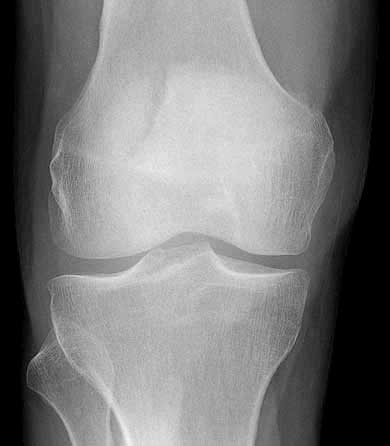

The second X-ray picture shows the knee with the leg stretched, seen from front. The patella is the faint whitish thing with a grey split in it.